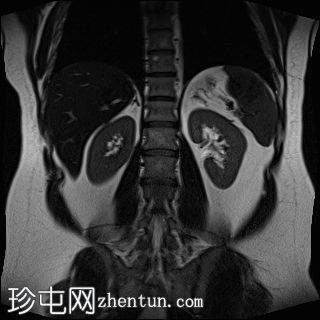

冠状位

T2加权像

T1低信号,T2低信号为主的脾脏肿块,内部可见T2高信号分隔,呈进行性强化。肿块中央可见星状瘢痕。

脾脏硬化性血管瘤样结节性转化(SANT),9.8 cm肿块

顾名思义,脾脏硬化性血管瘤样结节性转化(SANT)是一种纤维性血管病变。本病例展示了SANT的一些典型影像学特征,包括边界清晰的病灶,中央可见瘢痕,以及呈放射状进行性强化。这些特征使得术前MRI诊断较为明确。尽管SANT是一种良性病变,但大多数患者仍需行脾切除术以明确病理诊断。